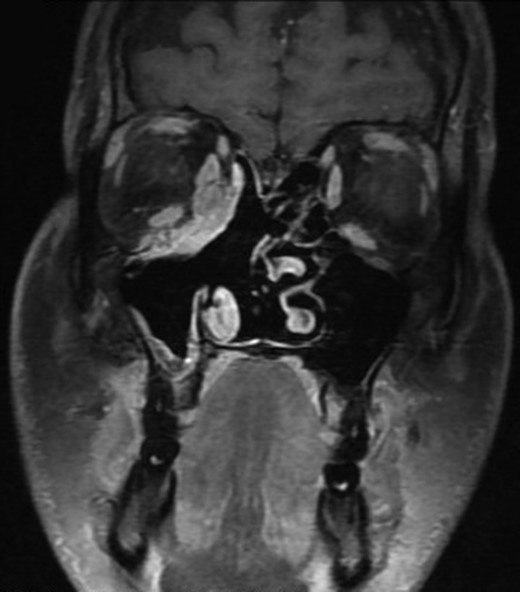

On radiological evaluation, CT scan with contrast of the paranasal sinuses (PNS) revealed a mass involving the right ethmoid sinus with medial wall and orbital floor extension (Fig. 2). The subsequent magnetic resonance imaging (MRI) revealed an infiltrative soft tissue mass occupying the right ethmoid sinus, eroding inferio-medial orbital wall and extending to the extracoanal space (Fig. 3). Positron emission tomography (PET) scan demonstrated an ill-defined 4.5 × 4.2 cm2 mass lesion in the right nasal cavity and ethmoid sinus extending to the right medial orbital floor (Fig. 4). The scan did not reveal any associated lymphadenopathies.

Magnetic resonance imaging (MRI) showing an enhancing soft tissue mass in the ethmoid sinus, eroding inferio-medial orbital wall.